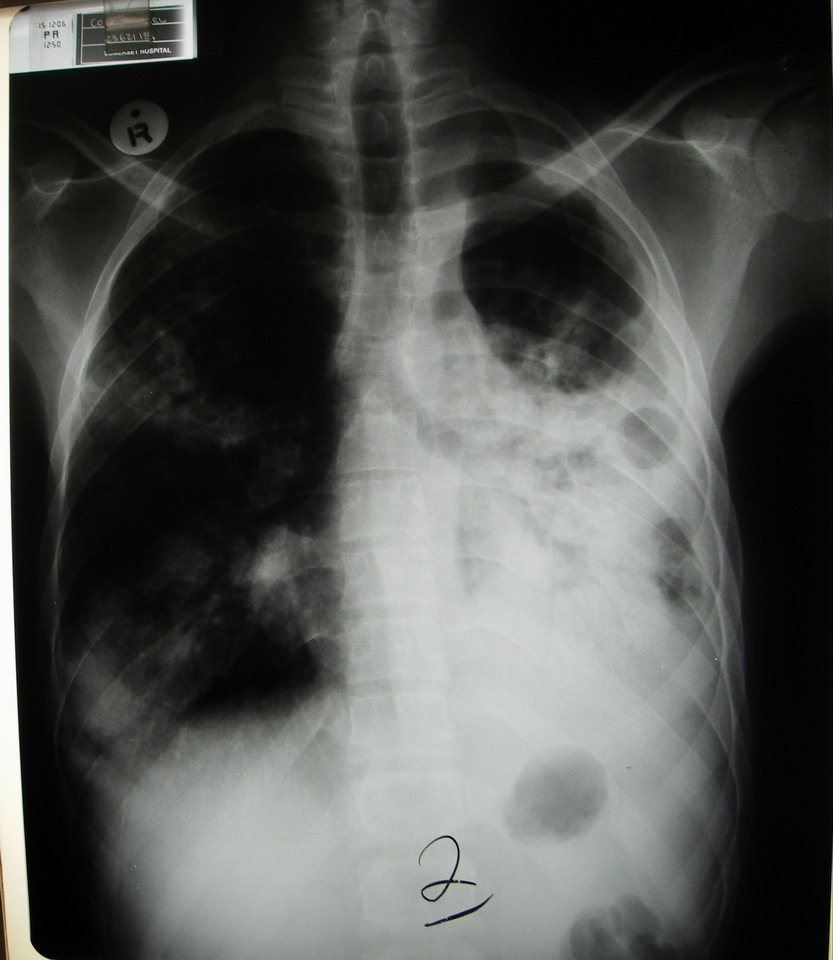

Cavitating mass in L lung -- for fun, let's poke this with a needle and see if we catch TB! |